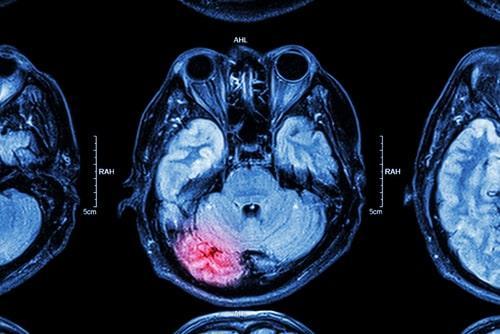

Next, head injuries are common in car accidents, particularly if a person is not wearing a seatbelt. Head injuries can range from mild concussions to more severe traumatic brain injuries. Severe traumatic brain injuries can have a long-lasting effect on a person’s cognitive abilities and overall quality of life.